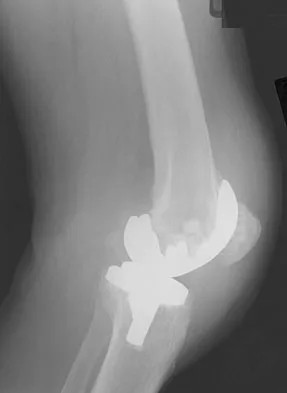

Figures 3a and 3b show the current radiographs of a 58-year-old man who underwent total knee arthroplasty with a cruciate ligament sparing prosthesis 7 years ago. Examination reveals boggy synovitis and moderate pain, particularly anteriorly. Management should consist of

Explanation

The patient has symptoms of synovitis that are most likely the result of the release of particles from the tibial polyethylene. While observation may be warranted in a completely asymtomatic knee, some intervention is indicated for this patient as there is clear radiographic evidence of lysis in both the tibia and femur. The decision about the extent of the revision should be made at the time of surgery. A limited incision technique is not indicated. Grafting (or using graft substitute) the defect is the most appropriate approach for treating the osteolytic lesions. While a posterior stabilized prosthesis might be the solution, surgical findings might dictate otherwise.